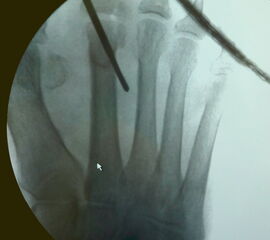

• Unter Durchleuchtungskontrolle Positionieren der Shannon-Fräse mit 20 mm langem und 2 mm dicken Fräsenkopf in 45° Neigung an den Hals des Metatarsale (siehe Abbildung 3 a und b).

• Verschieben der Fräsenspitze um wenige Millimeter nach proximal.

• Röntgenkontrolle, um die korrekte Position von Fräsenspitze bzw. Osteotomieebene an der distalen Diaphyse des Metatarsale-Knochens zu bestätigen (Abbildung 3 c).

Zum Lesen der Bildbeschreibung und zur Vollansicht bitte die Bilder anklicken. Bilder: A. Mehlhorn.